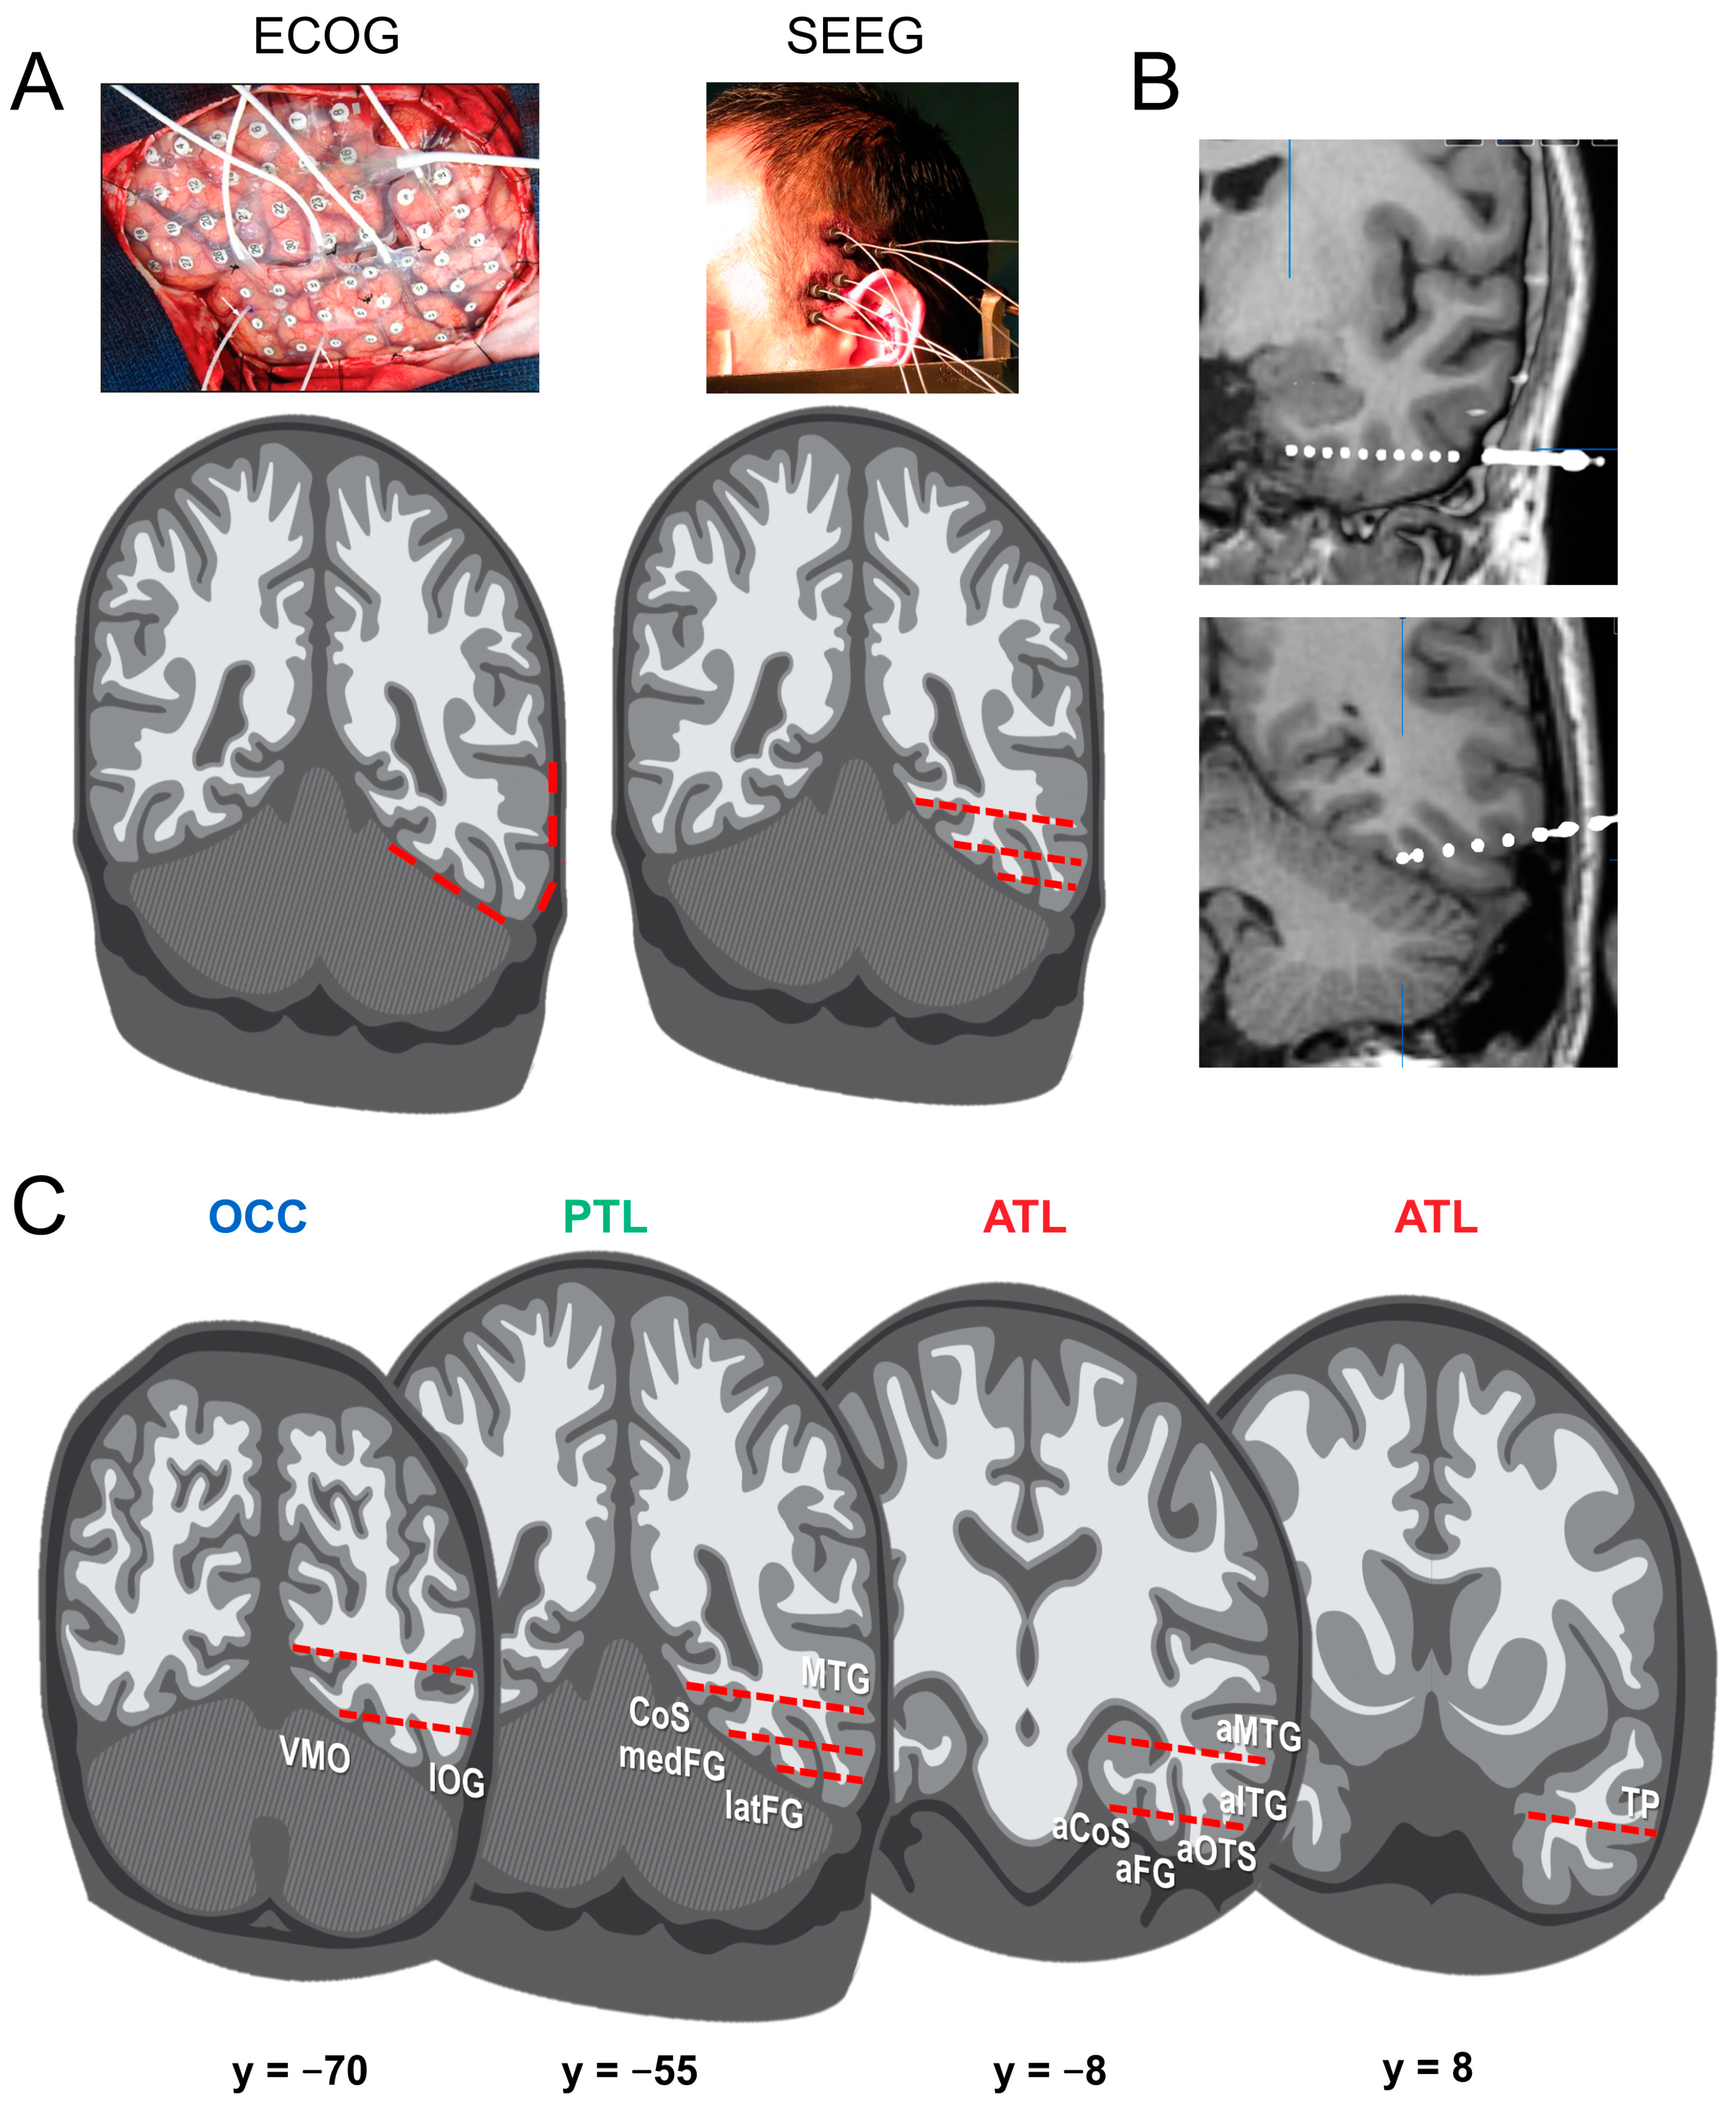

From a research perspective, the clinical procedure provides a unique opportunity to understand how the implanted brain regions contribute to recognition, in particular, face recognition. In practice, they are two surgical techniques for intracranial recordings (Figure 1). On the one hand, Electro-CorticoGraphy (ECoG) [28,29] consists in applying electrodes onto the cortical surface after removing part of the skull (i.e., subdural electrodes). Subdural electrodes have a circular shape and are spatially arranged as grids or strips with typically 5 to 10 mm inter-electrode spacing (center-to-center). On the other hand, Stereo-ElectroEncephaloGraphy (SEEG) [30,31] consists in inserting electrodes inside the brain, from the cortical surface to the medial cortex or medial temporal lobe structures (i.e., intracerebral electrodes, also often referred to as depth electrodes). The technique is called “Stereotactic” EEG because the implantation is based on a 3D coordinate system (the stereotactic frame), originally developed by Jean Talairach in the 1950s in Paris [32,33].

(A) Intracranial recordings in human epileptic patients are performed either with subdural grids of electrodes (Electro-CorticoGraphy, ECoG, on the left) or electrodes inserted inside the cortex and subcortical structures (Stereo-ElectroEncephaloGraphy, SEEG, on the right). In ECoG, part of the skull is removed to apply electrodes onto the cortical surface (here, grids of electrodes; see lower row for example electrode locations, in red, on a schematic coronal slice). In SEEG, small holes are drilled in the skull to implant thin depth electrodes. Lower row: Recording contacts from typical electrode trajectories are represented in red. The two techniques differ in terms of their advantages, both in terms of clinical investigations and associated research purposes. The present review focuses on SEEG, which is growing in usage across the world for clinical reasons (less invasive since there is no craniotomy, reduced incidence of infections, and hemorrhages; [31,34,35]. (B) Examples of SEEG electrodes in two patients as they appear when co-registering the pre-operative MRI with the post-operative CT-scan (white ‘dots’ on the coronal slices; top: electrode in the ATL, bottom: electrode in PTL targeting the latFG). Each electrode typically contains 8–15 contiguous individual recordings sites (or contacts). (C) Typical locations of electrodes implanted (across patients) in the ventral occipito-temporal cortex, as reviewed here (OCC: occipital; PTL: posterior temporal lobe; ATL: anterior temporal lobe. See below for abbreviations of specific cortical structures).

From the point of view of fundamental research, ECoG offers more extensive spatial coverage, perhaps more homogenous across individual brains. However, ECoG electrodes are limited to the gyral surface, providing a more limited sensitivity to sulcal neural activity. In contrast, SEEG penetrates the brain tissue and provides recordings directly inside the brain (i.e., not only intracranially, but intracerebrally), allowing to explore medial temporal lobe structures (e.g., amygdala, hippocampus; Figure 1B) and cortical sulci (which is particularly important given the high degree of cortical folding of the human brain, especially in association cortex [36]) (Figure 1C). The current intracerebral electrodes are thin cylinders (e.g., 0.8 mm diameter) typically containing 8–15 contiguous individual recordings sites (or contacts) of 2 mm length, separated by an insulating material (3.5 mm spacing, center-to-center).

- Studies are performed in large groups of implanted patients. In mapping studies of face recognition described below, all patients with at least one electrode in the ventral occipito-temporal cortex (VOTC, including the occipital lobe (OCC), Posterior Temporal Lobe (PTL), and Anterior Temporal Lobe (ATL) (Figure 1C)) are included, with samples of up to, e.g., N = 121 patients for some studies [37].